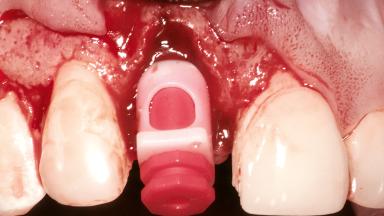

Replacement of a Maxillary Right Central Incisor Using an Early Loading Protocol

Bone Augmentation Horizontal|Simultaneous

Augmentation Materials Autogenous chips|Membrane

Soft Tissue Grafting Simultaneous

Placement Protocol Early or late implant placement

Bone Volume Deficient horizontally, allowing simultaneous augumentation